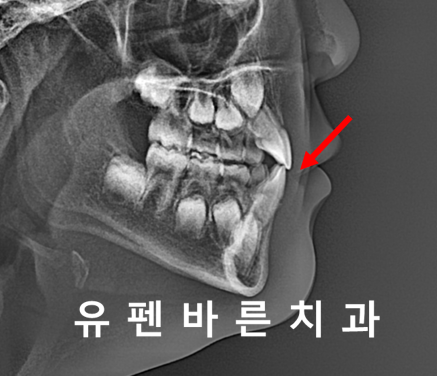

먼저 교정 시작을 위해

옆모습 엑스레이를 찍어보니

위, 아랫니의 앞니와

안쪽에 6세 어금니가

반대로 교합이 되는 상황 이었습니다